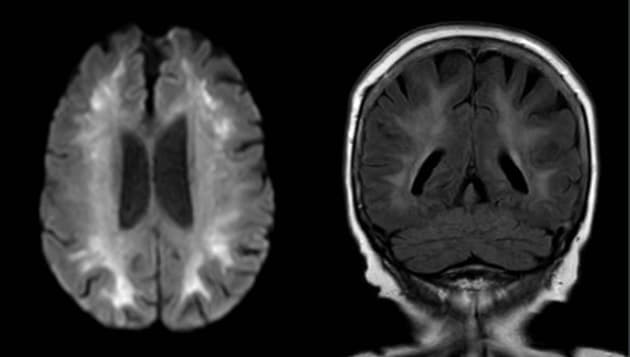

MR skanning af hjernen.

Sygehistorien beskriver en tidligere rask 77-årig kvinde, som blev fundet bevidstløs med svær kulilteforgiftning fra et defekt pillefyr. Arteriepunktur viste svært forhøjet hæmoglobinmætning af kulilte på 27%. Hun fik flere behandlinger med hyperbar oxygen i trykkammer og blev udskrevet efter otte dage. Ca. 3 uger senere blev hun genindlagt med balancebesvær, hukommelsesbesvær og apati. Læs mere om patogenese og diagnostik af denne tilstand, som benævnes forsinket neuropsykiatrisk syndrom, i kasuistikken af El Mahdaoui et al.